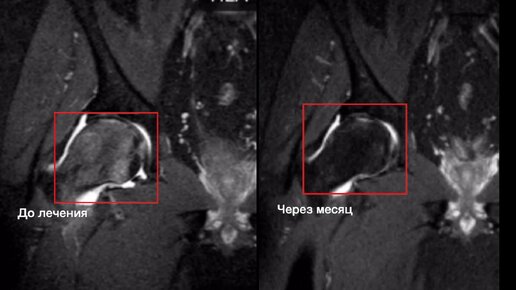

Авторская методика: безоперационное лечение тазобедренного сустава